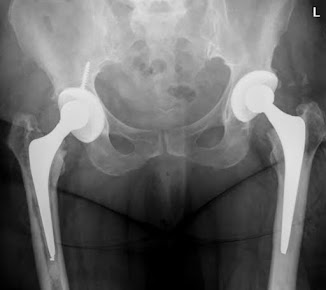

Hospital Gallery

The Veer Hospital is committed to providing affordable, quality health care to patients by incorporating improvement in its day-to-day schedule.